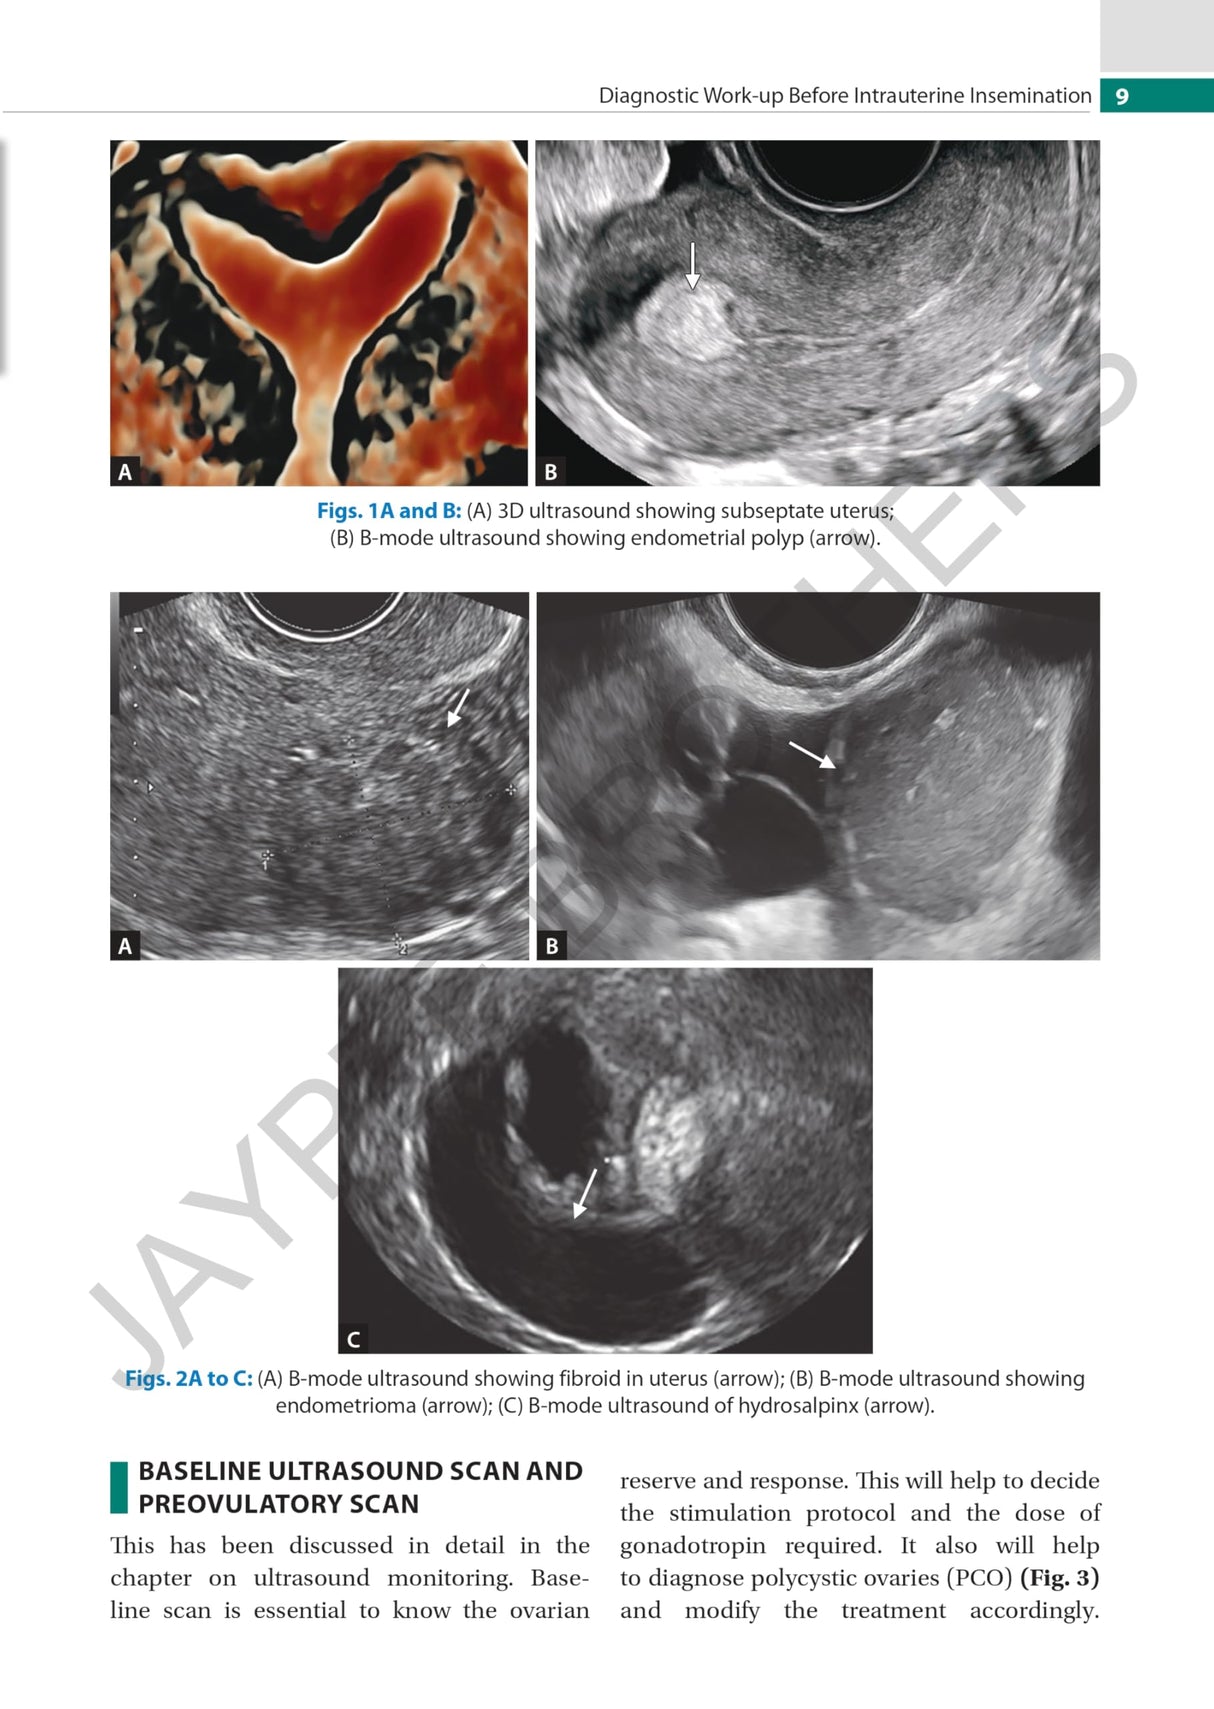

Beginning with discussion on counselling and diagnostic work-up before IUI, the next chapters cover indications and ultrasound. The following sections examine ovulation, timing of IUI, techniques, luteal phase support, complications, and factors affecting success. The final chapter discusses sperm preparation.

The text is further enhanced by clinical images and figures.